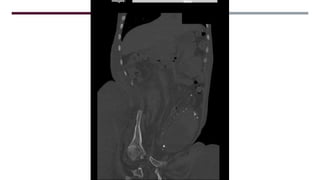

MASA SÓLIDO/QUISTICA

MESENTERIO/PERITONEO

LESION FOCAL PARED

ABDOMINAL

CALCIFICACION ESPLÉNICA